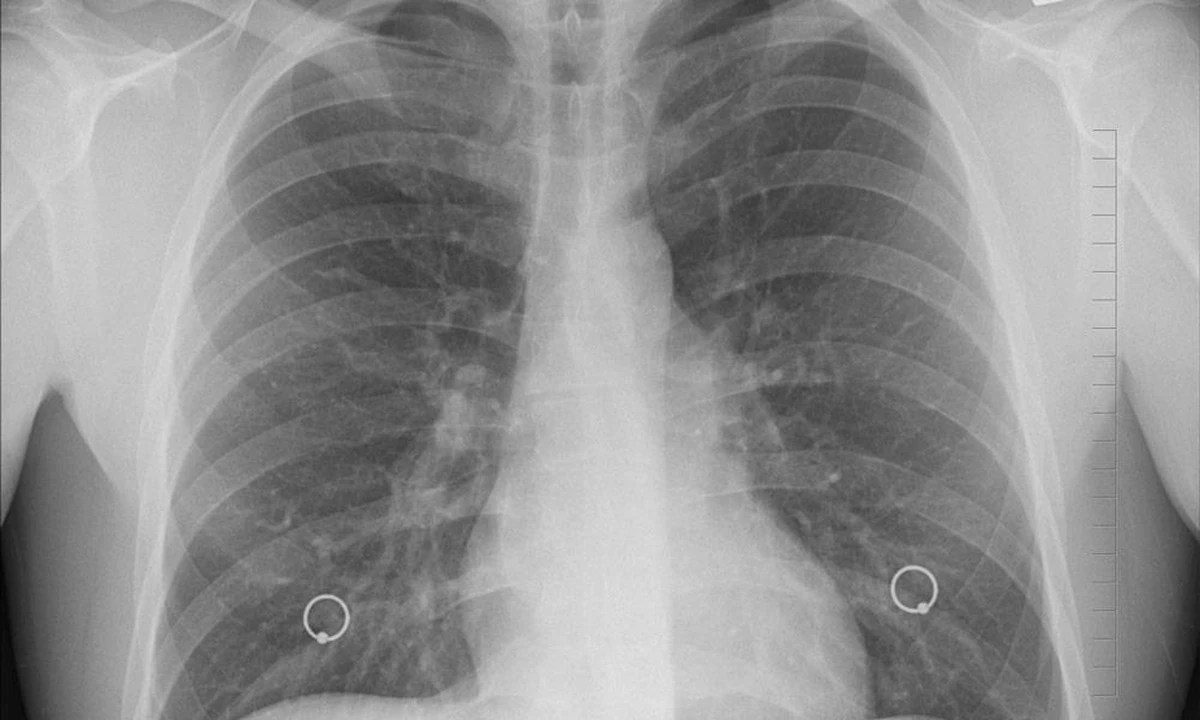

L’oncologo racconta il caso di una sua paziente che avvertiva un dolore al petto ogni volta che beveva vino. «Una paziente riferì un dolore al petto che durava uno o due giorni ogni volta che beveva un bicchiere di vino», ricorda Sekeres. Dopo gli esami, la Tac rivelò una massa ai polmoni e la biopsia confermò un linfoma di Hodgkin. Un episodio raro, ma rivelatore: un dolore circoscritto e ricorrente può essere un segnale da non ignorare.

Tac che mostra una massa polmonare